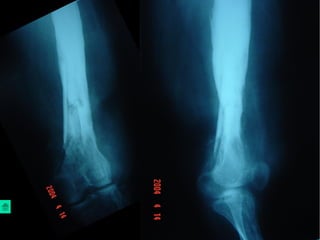

Giai đoạn mãn tính

Viêm xương chấn thương

Chẩn đoán

Lâm sàng:

Dò mủ kéo dài, đau nhức ít, không sốt hoặc sốt âm

ỉ, sưng nề khu trú

Xquang: Có thể thấy xương chết, xương tù, phản

ứng tạo xương ngoài màng xương

Chụp Xquang đường dò có cản quang: thấy được

ngóc ngách của đường dò đi đến đâu